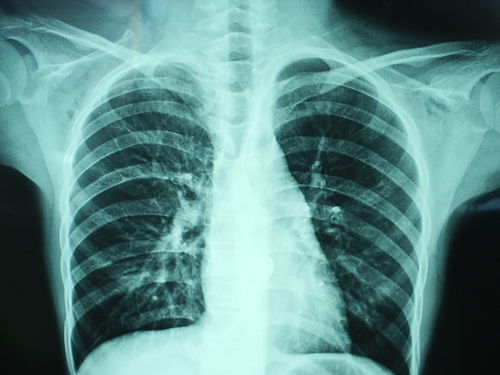

胸透可以看到胸部的軟組織、骨骼(包括胸椎)、縱隔(心臟、大血管、氣管、食管等)、氣管和支氣、胸膜、肺組織等??梢栽\斷肺和氣管的先天性疾病,如發(fā)育異常、肺部的各種炎癥、急慢性支氣管炎、比較明顯的支氣管擴張癥、肺氣腫或肺水腫、各型肺結核、肺腫瘤、胸腔積液、氣胸、縱隔腫瘤、心臟形態(tài)異常等

健康查體最常做的是胸部的X線(xiàn)檢查,最基本的就是胸透。 胸透可以看到胸部的軟組織、骨骼(包括胸椎)、縱隔(心臟、大血管、氣管、食管等)、氣管和支氣、胸膜、肺組織等。

可以診斷肺和氣管的先天性疾病,如發(fā)育異常、肺部的各種炎癥、急慢性支氣管炎、比較明顯的支氣管擴張癥、肺氣腫或肺水腫、各型肺結核、肺腫瘤、胸腔積液、氣胸、縱隔腫瘤、心臟形態(tài)異常等。